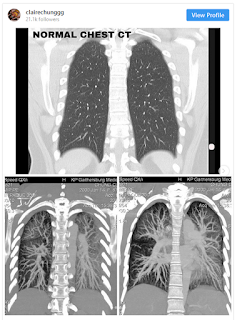

Berikutan itu, Claire sekali lagi memuat naik gambar yang menunjukkan imbasan sinar x pada paru-parunya yang kelihatan berkabus. Menerusi gambar imbasan paru-paru berkenaan, dapat dilihat bahawa kedua-dua belah paru-parunya kelihatan seperti berkabus, yang mana sepatutnya organ paru-paru yang sihat akan kelihatan jelas dalam imbasan.